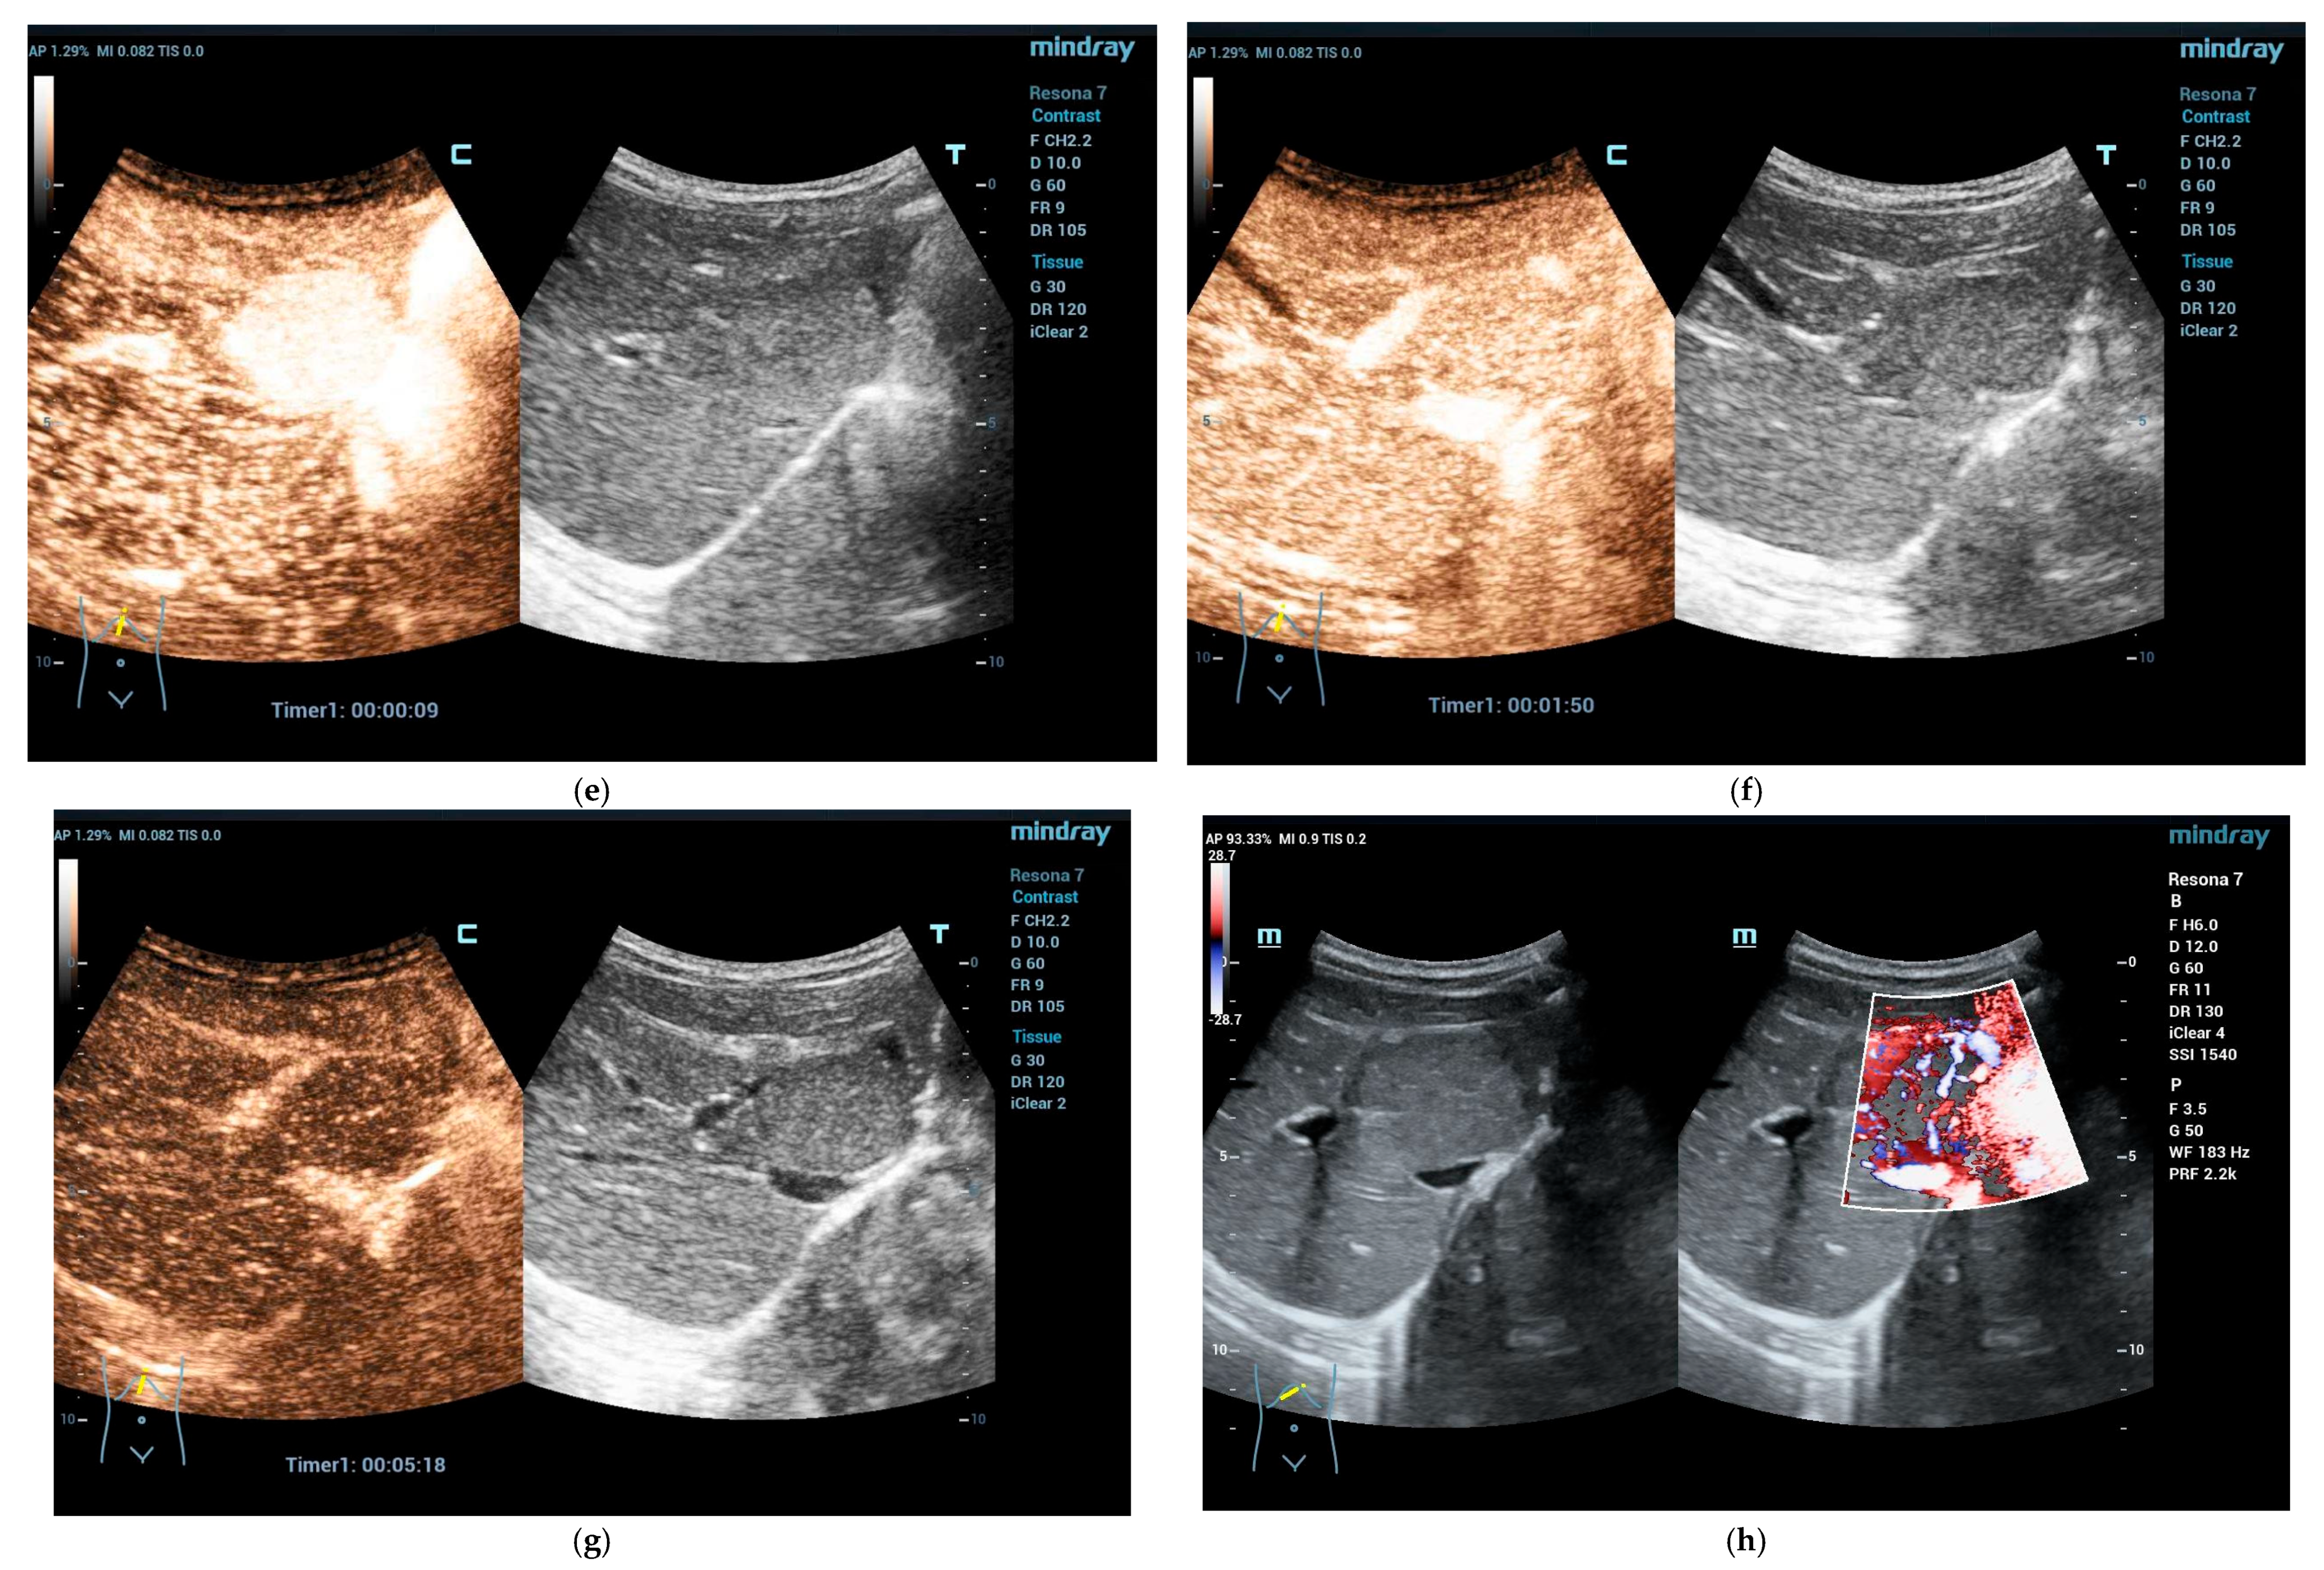

Focal Nodular Hyperplasia (FNH)

4.5. Hepatocellular Adenoma (HCA)

4.6. Inflammatory Hepatocellular Adenoma

4.7. HNF-1-Inactivated Hepatocellular Adenoma

4.8. β-Catenin-Activated Hepatocellular Adenoma